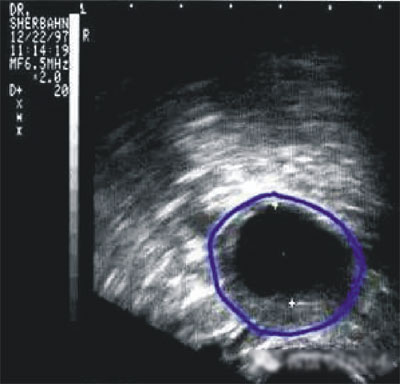

陰道B型超聲動(dòng)態(tài)監(jiān)測卵泡的發(fā)育及排卵,是監(jiān)測排卵最準(zhǔn)確可靠的方法。通過陰道B超檢查可以了解子宮及雙側(cè)附件(卵巢和輸卵管)區(qū)的基本情況,測定卵巢內(nèi)的竇卵泡計(jì)數(shù),評(píng)估卵巢儲(chǔ)備功能,動(dòng)態(tài)監(jiān)測排卵。